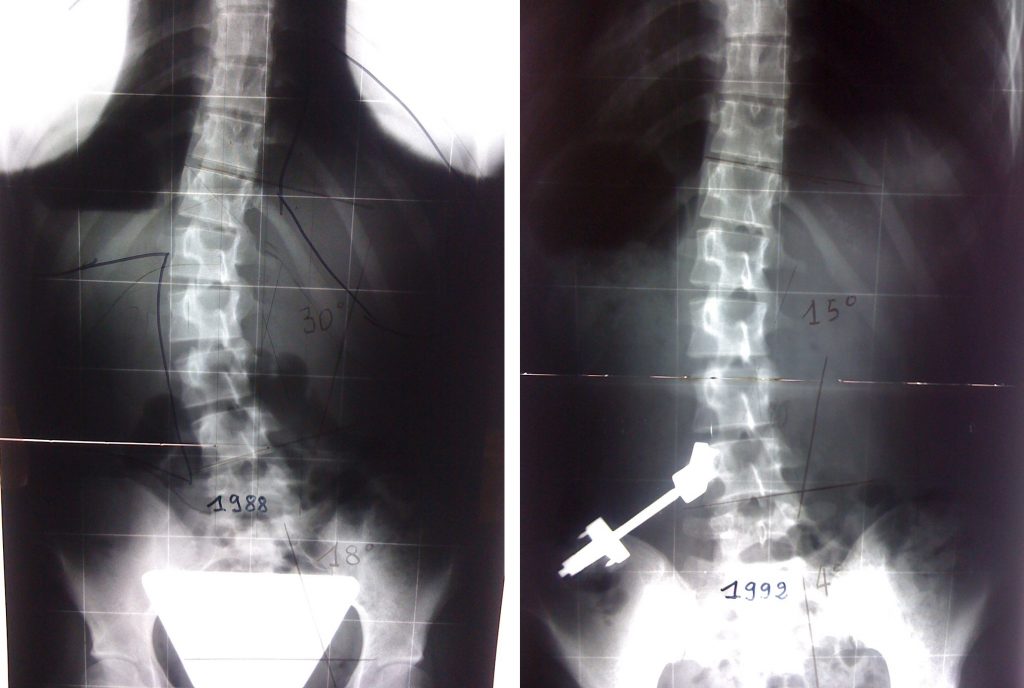

Matériel utilisé pour la réduction des scolioses lombaires en cours d’évolution. Mise en place d’un distracteur disposé entre la crête iliaque et la 4ème vertèbre lombaire.

Ce dispositif réduit la scoliose en horizontalisant la 4ème lombaire, bloquant l’évolution de la scoliose jusqu’à la fin de la croissance ou il est enlevé, l’espace recouvrant sa mobilité.